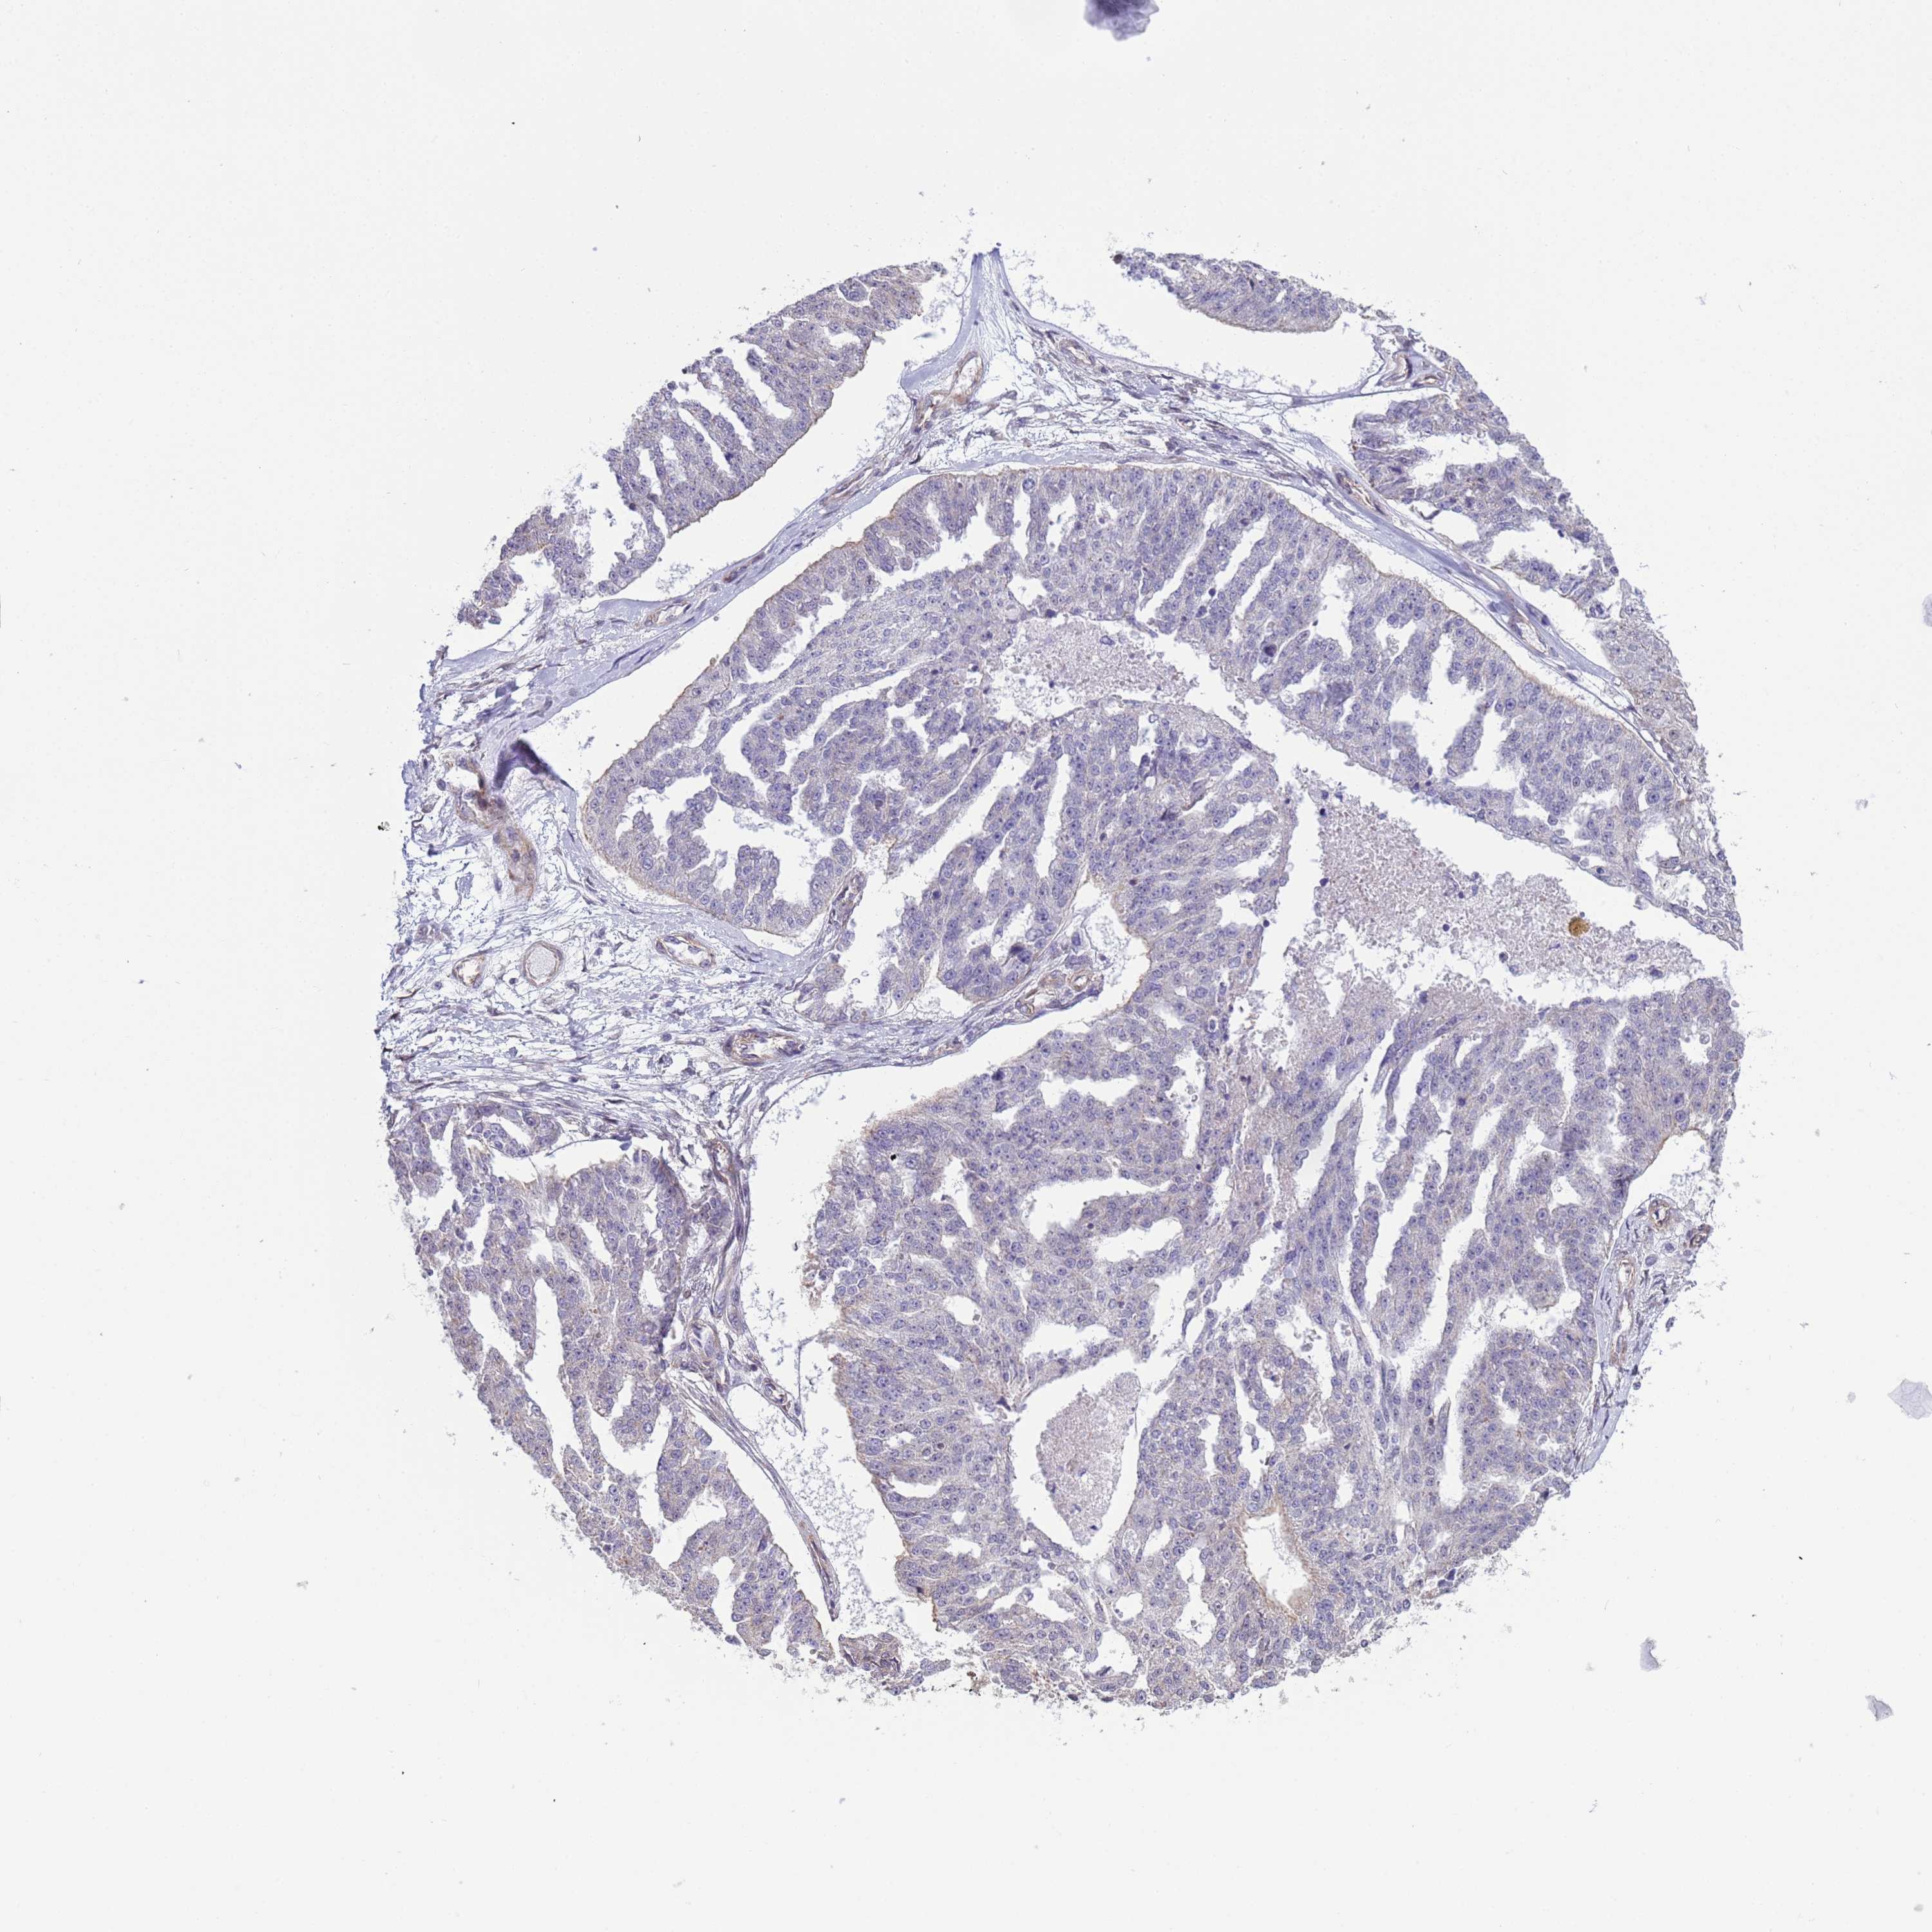

OVARIAN CANCER - Protein expressioni

A mouse-over function shows sample information and annotation data. Click on an image to view it in a full screen mode. Samples can be filtered based on level of antibody staining by selecting one or several of the following categories: high, medium, low and not detected. The assay and annotation is described here.

Note that samples used for immunohistochemistry by the Human Protein Atlas do not correspond to samples in the TCGA dataset.

Antibody stainingi

Antibody staining in the annotated cell types in the current human tissue is reported as not detected, low, medium, or high, based on conventional immunohistochemistry profiling in selected tissues. This score is based on the combination of the staining intensity and fraction of stained cells.

Each image is clickable and will lead to virtual microscopy that enables deeper exploration of all samples and also displays staining intensity scores, fraction scores and subcellular localization as well as patient and tissue information for each sample.

Antibody HPA036348

Antibody HPA036349

Antibody CAB002422

Antibody CAB005258

Cystadenocarcinoma, serous, NOS

Carcinoma, NOS

Cystadenocarcinoma, mucinous, NOS

Carcinoma, endometroid